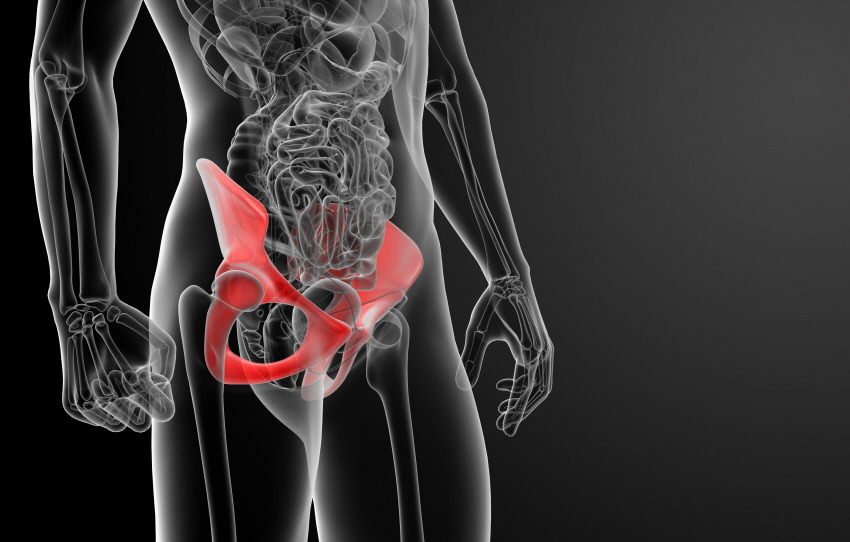

골반은 우리 신체의 가운데에서 척추를 지지하면서 체중을 다리로 분산하는 역할을 하고 있습니다. 즉, 몸의 균형을 잡아주는 기관으로 골반이 틀어지면 양쪽 다리 길이에 차이가 생기고, O자 다리, X자 다리 등 하체 변형과 각종 척추 질환의 원인이 되므로 교정하는 것이 중요합니다.

콕통증의학과에서는 ‘오늘부터 시작할 수 있는 골반교정 방법’을 소개해드릴게요.